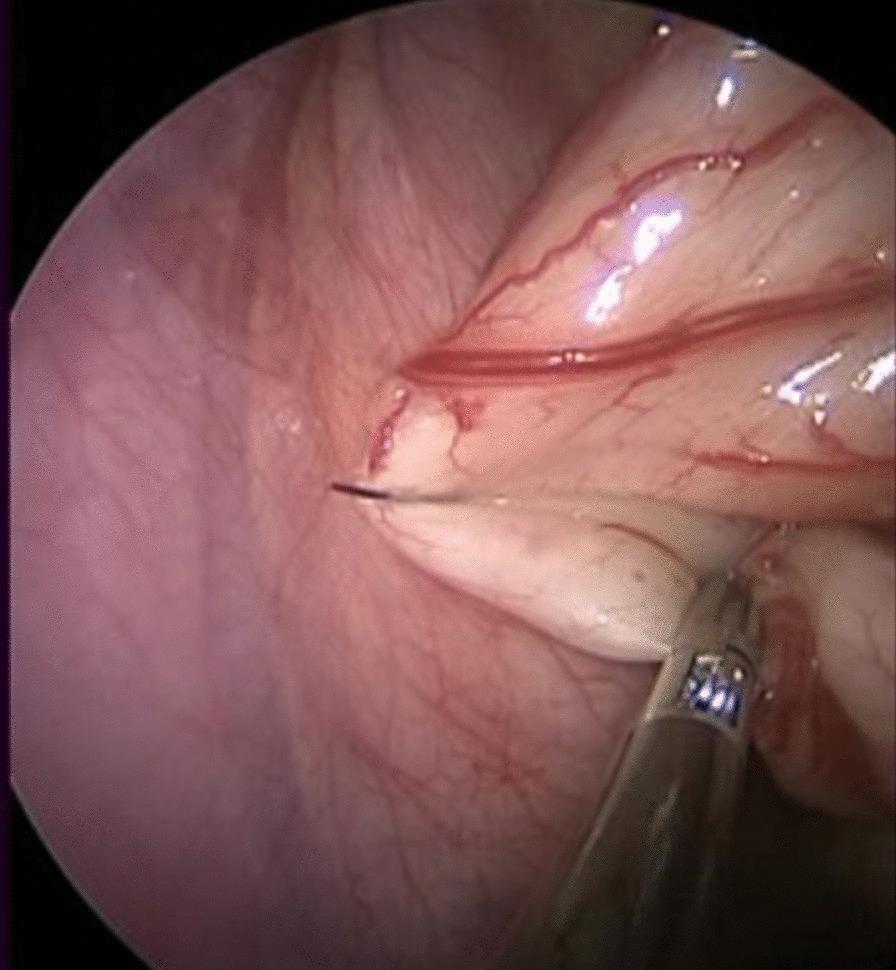

The procedure began with a 1 cm transumbilical skin incision. Three separate punctures were made in the fascia with a 5 mm scope in the middle and 5 mm and 3 mm ports for working instruments on the left and right, respectively. The first suspension suture was placed to secure the sigmoid colon to the abdominal wall. A window was created through the rectal mesentery, and dissection around the rectum was carried out. The second suspension suture was performed to suspend the rectovesical peritoneal fold or the rectovaginal peritoneal fold to the abdominal wall. Dissection around the rectum was continued downward to approximately 1 cm below the peritoneal fold. Then, the operation was completed by a transanal approach.

手术始于脐部 1cm 的小切口。在筋膜上分别做三个 5mm 的穿刺孔,中间一个用于放置 5mm 腹腔镜,左右两侧分别用于放置 5mm 和 3mm 的操作器械。首先放置第一根悬吊缝线,将乙状结肠固定于腹壁。通过直肠系膜开窗,游离直肠周围。然后进行第二根悬吊缝线操作,将直肠膀胱腹膜反折或直肠阴道腹膜反折悬吊于腹壁。继续向下游离直肠周围组织,直至腹膜反折下方约 1cm 处。最后经肛门完成手术操作。